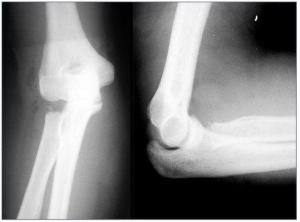

桡骨头骨折是成年人容易发生的肘部损伤,多为在平地跌倒或体育运动时致伤,通常疼痛症状较轻。人在跌倒时,肘关节伸直并在肩关节外展位手掌着地,使肘关节置于强度的外翻位,导致桡骨头猛烈地撞击肱骨小头,引起桡骨头骨折。